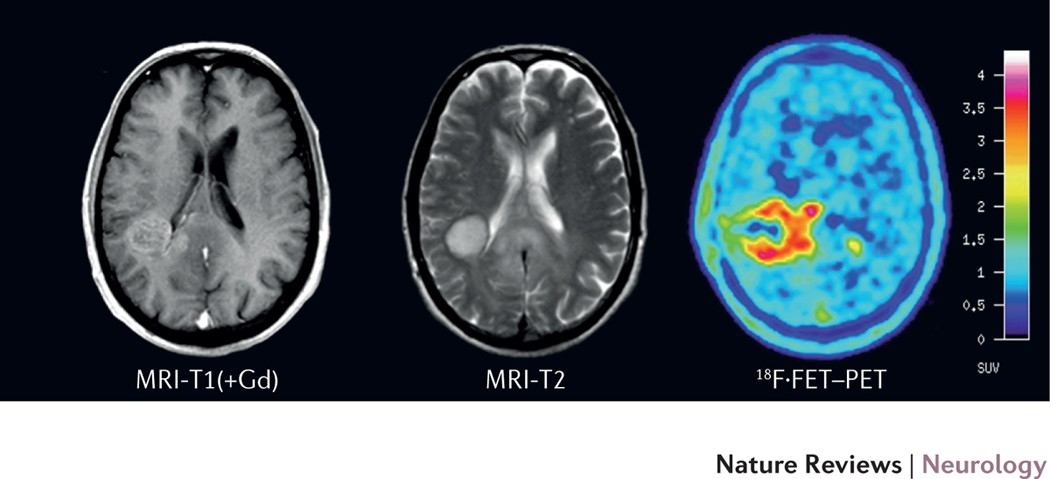

A CT scan can help find bleeding and enlargement of the fluid-filled spaces in the brain called ventricles. A combined PETCT exam fuses images from a PET and CT scan together to provide detail on both the anatomy from the CT scan and function from the PET scan of the brain. A ct scan will show brain tumors if they are large enough have calcium or blood in them or are causing swelling.

There are brain tumors with an intact BBB notably most low-grade gliomas LGG which may be missed on a contrast-enhanced CT scan but are easily detected by increased signal as a.

Multimodality Assessment Of Brain Tumors And Tumor Recurrence Journal Of Nuclear Medicine